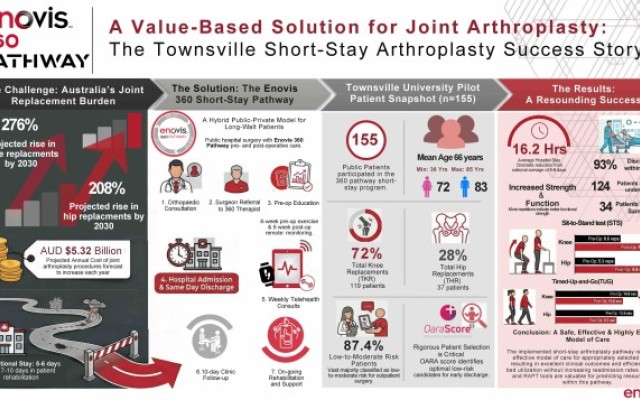

Day Surgery Arthroplasty

Introduction

Elective joint replacement surgery in the Australian public hospital system has traditionally been associated with long inpatient stays, averaging 5–6 days, followed by 7–10 days of inpatient rehabilitation. This model is costly, inefficient, and contributes to extended wait times for patients. With the projected rise in joint replacements—276% for knees...